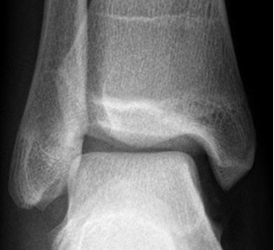

La Rx puede ser normal o mostrar edema de tejidos blandos. (12). (Fig 58 A y B).

Fig 58 A. Esguince del tobillo.

Rx AP. Edema de tejidos blandos, sobre el maléolo externo.